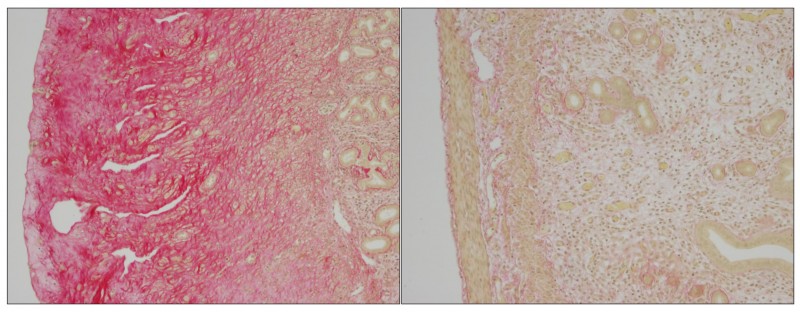

EPFL scientists have identified the biological mechanism behind the painful, potentially lethal, disfiguring Hyaline Fibromatosis Syndrome. Image caption:â?Loss of ANTXR2 leads to the accumulation of extracellular material in mice uterus and sterility (Left). Collagen 6 removal in mice without ANTXR2 restore uterine structure and function (Right). This result indicates that collagen 6 accumulation is the cause of uterine tissue disruption in mice devoid of ANTXR2, the latter playing a crucial role in collagen 6 degradation. Hyaline Fibromatosis Syndrome (HFS) is a rare but severeâ'genetic disease that affectsâ'babies, children, and adults. A glassy substance called hyalineâ'accumulates in the skin and various organs of patients, causing painful deformities and may lead to early death.â'The disease is caused by geneâ'mutations that destroyâ'the function of a protein whoseâ'physiological function is little understood.â'EPFL scientists have now studied and characterized its function for the first time, showing that it binds and controls the body levels of an important type of collagen. The work is published .